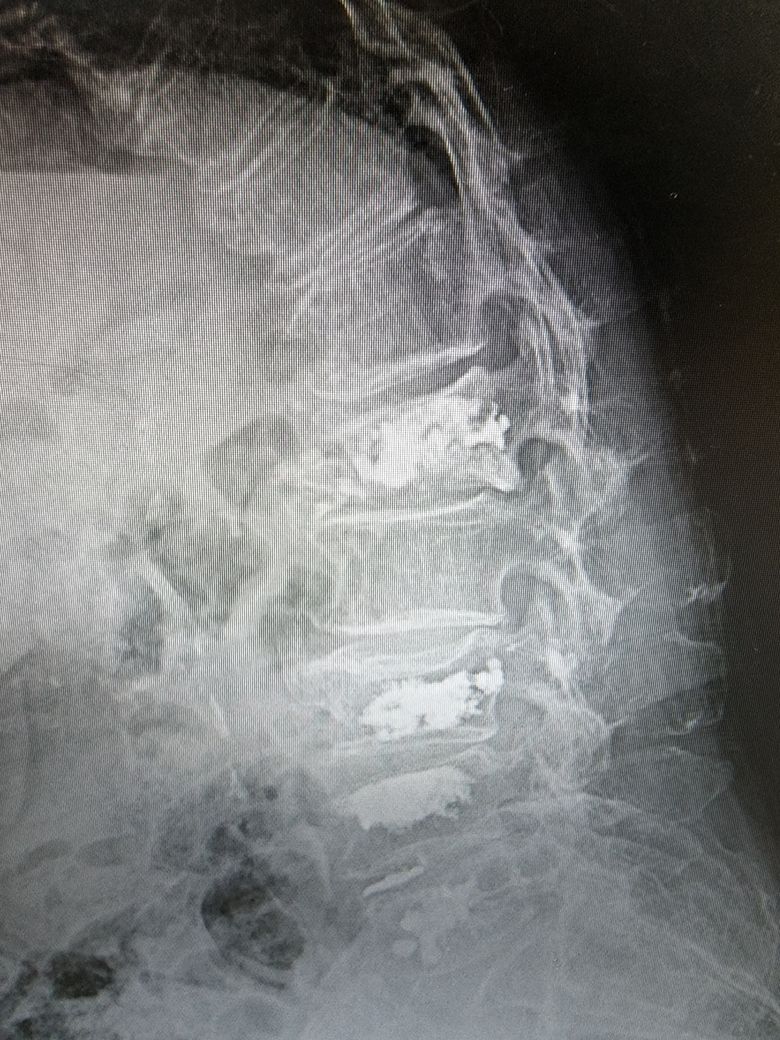

78세인 어머니께서 3월에 척추압박골절로 4번째 골시멘트성형술을 받으셨습니다. 요추3번4번5번 이번엔 1번이 골절되어서 극심한 통증으로 시술을 받으셨고 전에는 하루만에 통증이 사라졌으나 이번에는 시술후에도 계속되는 통증으로 고생하셨습니다. 참다참다 일주일후 다시 병원가서 mri검사를 해보니 시술한부위 뒷쪽뼈에 멍이 들어있다며 주저앉았냐고 의사선생님이 물어보시더군요. 그런적없다고..

입원해서 통증치료하자며 20일 가까이 보존치료로 진통제 맞으며 지내다가 연결해주는 다른병원에서 14일 입원후 퇴원했는데도 계속 통증을 호소하시네요.

답답해서 지난주 다시 병원에서 mri검사를 했습니다. 특이한 사항이 없다? 더이상 해줄것이 없다고 말씀하시더군요.

• 1번 째 사진

• 2번 째 사진